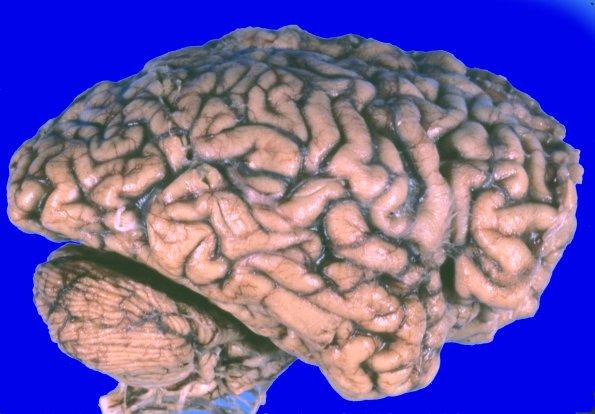

At autopsy the brain weighed 670g. ---- 7A1,2 External examination of the brain showed marked diffuse cortical atrophy.